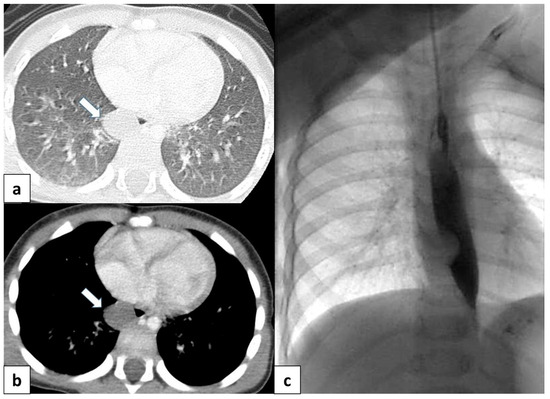

3.6.1. Pulmonary Sequestration

3.6.2. Hypogenetic Lung Syndrome